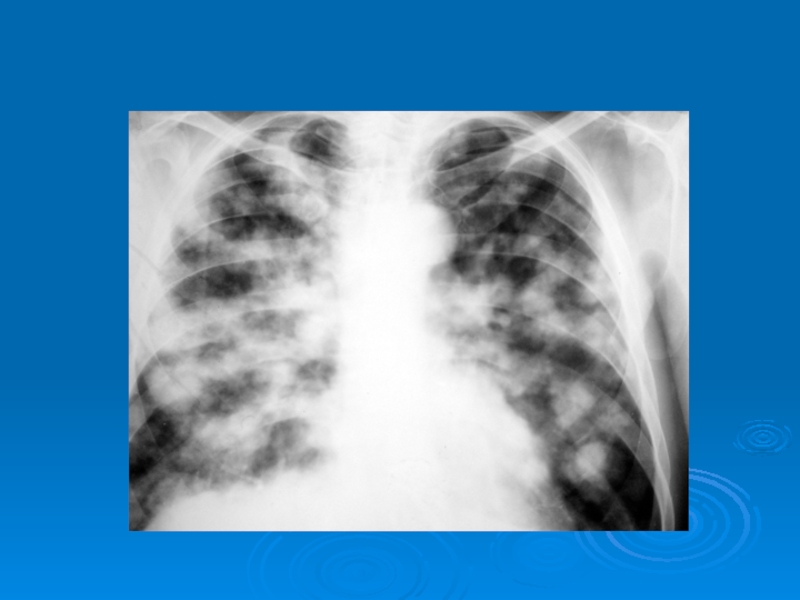

Слайд 43Распространенные диффузные диссеминации (метастазы злокачественной опухоли)

Распространенные диффузные диссеминации (метастазы злокачественной опухоли)